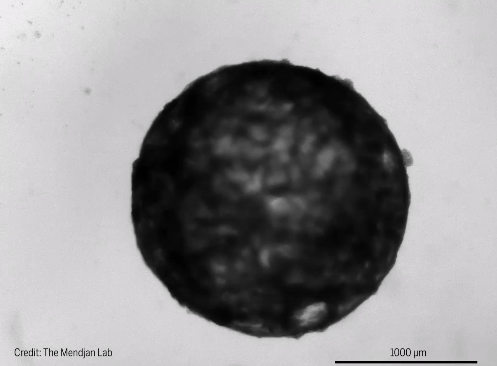

發育1周後,類器官在結構上相當於25天胚胎的心臟。在這個階段,心臟只有一個心室,這將成為成熟心臟的左心室。類器官直徑約為2毫米,包括這一發育階段常見的主要細胞類型:心肌細胞、上皮細胞、成纖維細胞和心外膜。它們也有一個清晰的心室,每分鐘跳動60到100次,這與相同年齡的胚胎心臟的速率相同

對於此次創造出的迄今為止最真實的心臟類器官,Mendjan

表示,當其第一次看到它的時候,很驚訝這些心室可以自行形成。相比其他類器官,心臟類器官的成敗顯而易見,它會跳動。迄今為止,這顆“迷你心臟”已經在實驗室中存活了3個多月,它將幫助科學家們瞭解心臟發育的前所未有的細節。